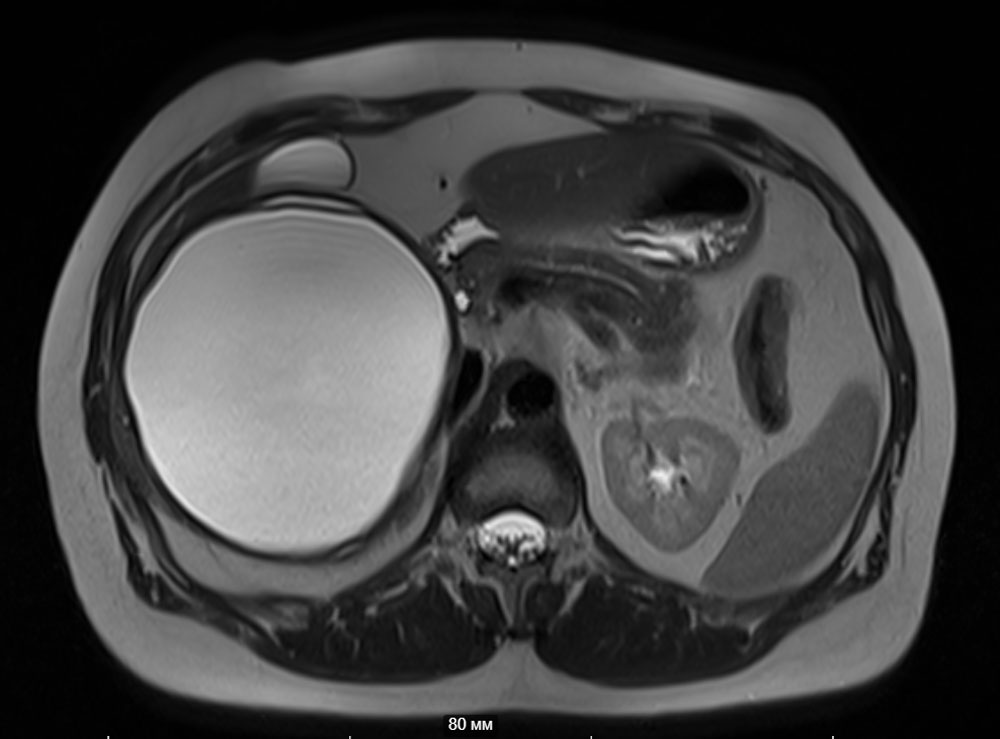

С целью диагностики и определения тактики лечения используются лабораторные и инструментальные методы: стандартные анализы дополняются серологическими тестами на выявление паразитарной активности и опухолевыми маркёрами (СА19,9; РЭА); ультразвуковая диагностика, компьютерная томография с внутривенным контрастированием, магнитно-резонансная томография. В Пироговском Центре возможно прохождение всех этапов диагностики на самом современном оборудовании (рис. 3, рис. 4).